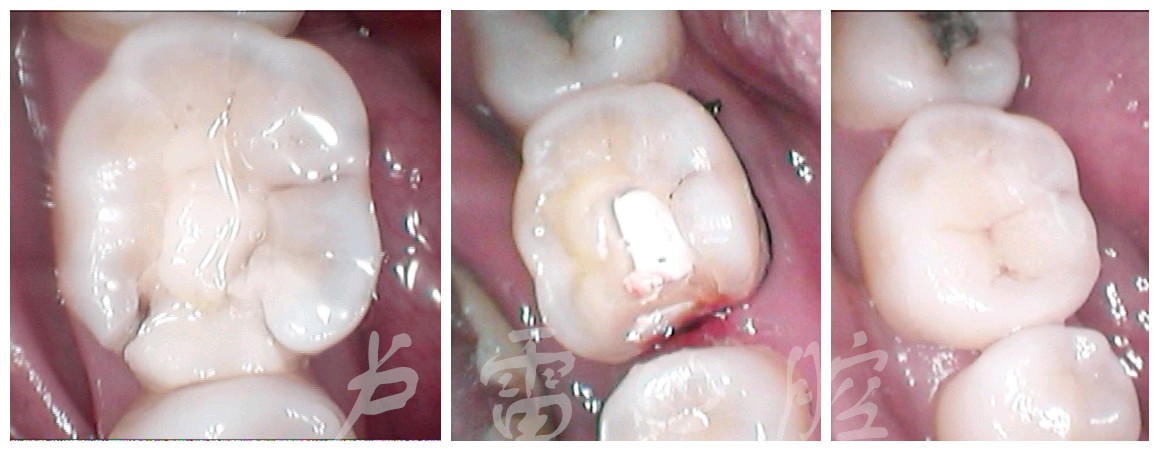

第二类是发生在后牙邻面的龋齿所制备的洞,叫做Ⅱ类洞(图二)。

图二

处理方案:1、全瓷嵌体

2、硬度高的材料补牙

3、全瓷冠修复

分析:因为二类洞是两牙之间的边缘洞,洞的周围少了一个面牙壁,而且洞的两边牙壁很薄,容易断裂。1、所以选择硬度高,又可以保护比较薄的牙壁不容易断裂,第一选择是全瓷嵌体,属于微创修复。2、因补牙材料硬度有限,起不到护薄的牙壁,如补牙材料选择不当,补牙后咀嚼比较硬的食物牙齿薄壁容易断裂和补牙材料脱落,导致食物嵌塞,补牙失败。3、全瓷冠修复,需要把牙齿磨小,对牙齿有一定的损害,不适很微创,所以全瓷冠是次次选择。